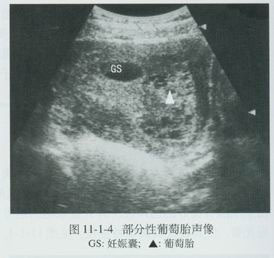

恶性葡萄胎六、无胎儿可及闭经8周前后,B超监测,未发现有胎囊、胎心及胎儿。孕周、甚至18周仍不感有胎动,听不到胎心。B超扫描显示雪片样影象而无胎儿影象。 医学百科网 | YxBaike.Com

七、卵巢黄素化囊肿往往在部分患者出现卵巢黄素化囊肿,可经双合诊发现或更易经B超检查发现。